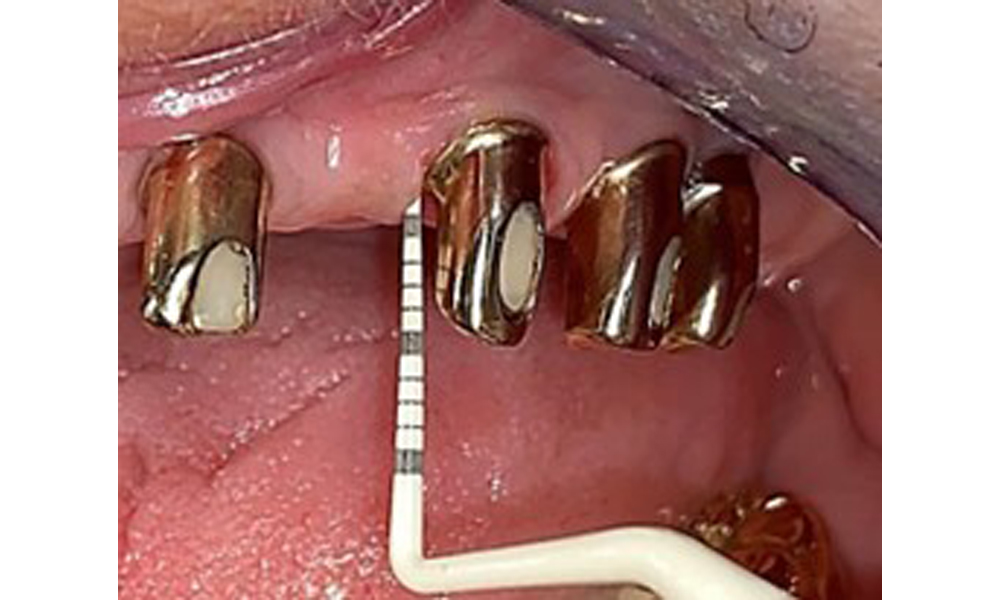

The patient was fitted with a combined removable maxillary telescopic prosthesis more than 25 years ago (Fig. 1, Fig. 2, Fig. 3) and is very happy with her dentures. The patient has an adequate fixed denture for the mandible (Fig. 4).

The dental findings are as follows: Combined removable implant and tooth-supported telescopic prostheses on implants 15, 13, 21, 23, 24, 25 and tooth 11 (Fig. 1, Fig. 2, Fig. 3). The patient was fitted with a fixed mandibular denture. Adequate bridges were present over 37 to 34 and 45 to 47 (Fig. 4), the crown margins were intact and there were no active caries. A composite filling with a marginal gap was present on tooth 43. There was mandibular gingival recession, exposing 1 to 3 mm of root surface. This also applies to 11.

Occlusal view of the mandible.

Fig. 4: Occlusal view of the mandible.